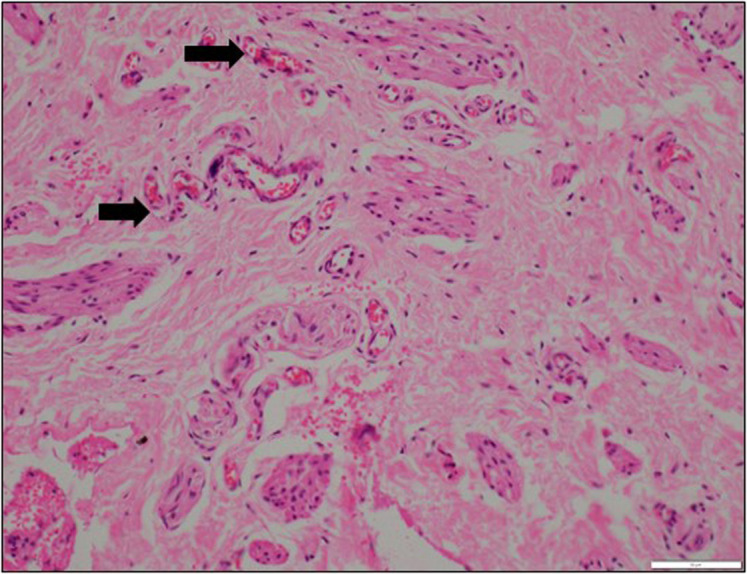

目的:包皮皮瓣在尿道下裂修复中应用广泛,但包皮组织的愈合潜力仍然是一个值得关注的问题。本研究旨在评估尿道下裂患者包皮与对照组相比的微血管密度(MVD)和生长因子受体(VEGFR和TGF-!R)水平,并比较包皮内外层的这些参数,以确定其在尿道下裂修复中的相对适宜性。方法:该研究包括14岁以下接受原发性尿道下裂手术的儿童和接受选择性包皮环切术的个体作为对照。取内包皮和外包皮标本,用CD31抗体进行免疫组化染色,评估MVD、VEGFR和TGF-!R抗体评估生长因子水平。用组织学评分系统半定量分析染色强度。结果:内包皮微血管密度显著高于外包皮(P < 0.05),提示内包皮组织在尿道下裂修复中具有潜在优势。相反,在病例中,外包皮的VEGFR水平显著高于外包皮(P < 0.05),表明这两层之间的愈合潜力不同。转化生长因子!对照组内包皮和外包皮的受体水平均显著低于对照组(P < 0.05)。其他研究结果均无统计学意义。结论:内包皮较高的MVD可能是尿道下裂修复的首选方法。然而,内包皮和外包皮之间VEGFR水平的差异突出了复杂的愈合动力学,强调需要进一步研究以得出明确的结论。

Objective: Preputial flaps are frequently used in hypospadias repair, but the healing potential of preputial tissue remains a concern. This study aimed to evaluate the microvessel density (MVD) and growth factor receptor levels (VEGFR and TGF-!R) in the prepuce of patients with hypospadias compared to controls and to compare these parameters between the inner and outer preputial layers to determine their relative suitability for hypospadias repair. Methods: The study included children under 14 years of age undergoing primary distal hypospadias surgery as cases and individuals undergoing elective circumcision as controls. Specimens from the inner and outer prepuce were collected, and immunohistochemical staining was performed using CD31 antibodies to assess MVD and VEGFR and TGF-!R antibodies to evaluate growth factor levels. The staining intensity was semi- quantitatively analyzed using a histological scoring system. Results: Microvessel density was significantly higher in the inner prepuce than the outer prepuce in both cases and controls (P < .05), suggesting a potential advantage of inner prepuce tissue in hypospadias repair. Conversely, VEGFR levels were significantly higher in the outer prepuce in cases (P < .05), indicating different healing potentials between these layers. Transforming growth factor ! receptor levels were significantly lower in both the inner and outer prepuce of controls compared to cases (P < .05). Other findings did not reach statistical significance. Conclusion: The higher MVD in the inner prepuce suggests it may be preferable for hypospadias repair. However, the differential VEGFR levels between the inner and outer prepuce highlight complex healing dynamics, emphasizing the need for further research to draw definitive conclusions.